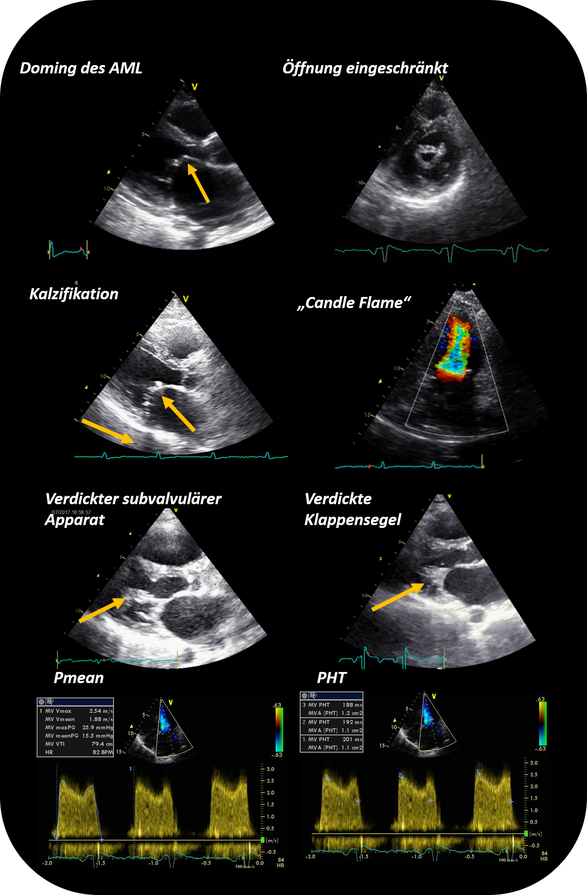

Eine detaillierte Beschreibung zur Evaluierung und Quantifizierung einer Mitralstenose mittels transthorakaler Echokardiographie findet sich in der Leitlinie von Baumgartner et. al. (Eur. J. Echocardiogr. 2009). Wichtiger in diesem Zusammenhang stellt die rezentere Leitlinie zur Abklärung und Therapie von Herzklappenerkrankungen dar (Praz et. al. Eur. Heart J. 2025).